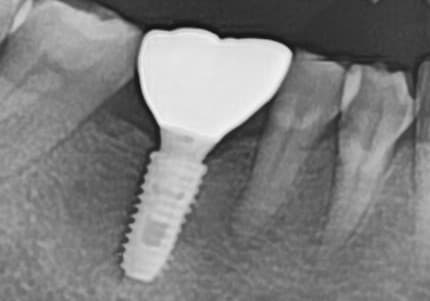

실제 치료 사례

정기적인 잇몸 치료로 임플란트 없이 건강한 치아 유지

"뼈가 심하게 녹았는데

잇몸치료로 뼈가 차올랐어요"

Before

After

심한 잇몸병으로 뼈가 많이 녹은 상태

잇몸치료와 뼈이식으로 뼈 재생 후 임플란트 식립